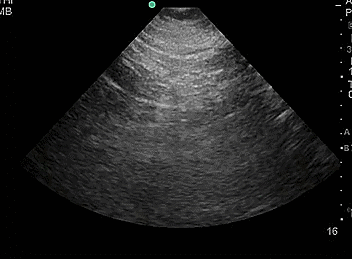

- Obtain longitudinal (long axis) and transverse (short axis) views. On longitudinal view the kidney will appear football-shaped and on transverse view the kidney appears C-shaped.

Video 1. Longitudinal view of normal right kidney